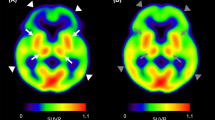

Mean tissue–time activity curves for the basal ganglia (BG) and cerebellum (Cb), the two regions of interest, from the first PET study (n = 5 monkeys) are shown in Figure 1 (top panel, closed symbols). For all monkeys initially anesthetized with 5% isoflurane and maintained on 1.5% isoflurane (Study 1), there was a high uptake of [18F]FCP and a linear rate of washout from the BG, a region with a high density of D2 receptors. Uptake of [18F]FCP in the Cb, a region devoid of D2 receptors, was lower, and the rate of washout was faster than that observed in the BG. When the monkeys were initially anesthetized with 10 mg/kg ketamine (Study 2) before the PET study (Figure 1, top panel, open symbols), there were no apparent differences in tissue–time activity curves compared to the first PET scan.

The mean BG:Cb distribution volume ratio (DVR) of [18F]FCP for Study 1 was 2.48 (±0.12), with a between-subject range of 2.29 to 2.89 ( Table 2). The mean DVR of [18F]FCP for Study 2 was 2.50 (±0.10), with a between-subject range of 2.27 to 2.83 (Table 2). Direct comparisons between Study 1 and Study 2 revealed within-subject variability of DVRs of approximately 2%; these differences were not statistically significant (t[4] = 0.64, p > .55). Graphical representation of BG:Cb time activity curve ratios for the isoflurane- and ketamine-induced anesthesia studies is shown in Figure 1 (bottom panel). As reported previously for this ligand (Mach et al. 1996), the rapid rate of washout of [18F]FCP from the BG and Cb resulted in a high BG:Cb ratio, reaching a peak value of 3.46 (±0.31) at approximately 65 min postinjection in Study 1, when anesthesia was induced by isoflurane. In Study 2, the mean peak BG:Cb ratio was 3.42 (±0.22) at 65 minutes postinjection. There were no statistically significant differences in the BG:Cb ratios (t[4] = 0.23, p > .82) between Study 1 and Study 2. Arterial plasma radioactivity curves and metabolite corrected plasma curves were not significantly different between the first and second PET studies (data not shown) and are similar to data reported previously for this ligand (Mach et al. 1996).